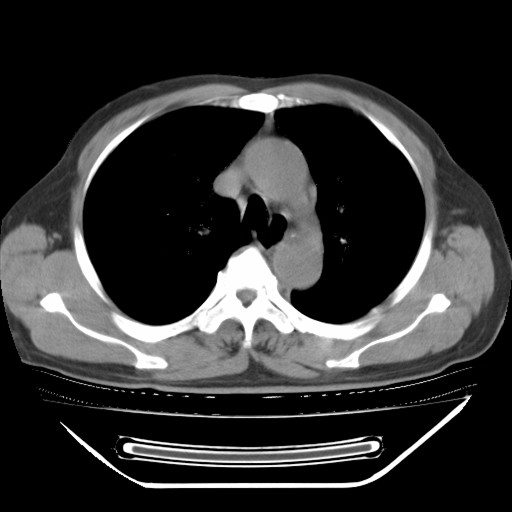

以下是引用hhcckk在2009-5-29 10:34:00的发言:[br]左下肺片絮状边缘模糊影,考虑感染,建议治疗后复查[br]